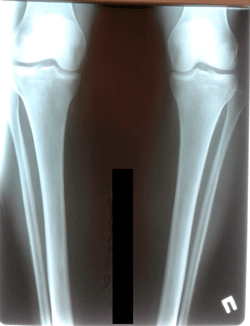

перед крутками

image-21-11-20-05-11-3.jpg